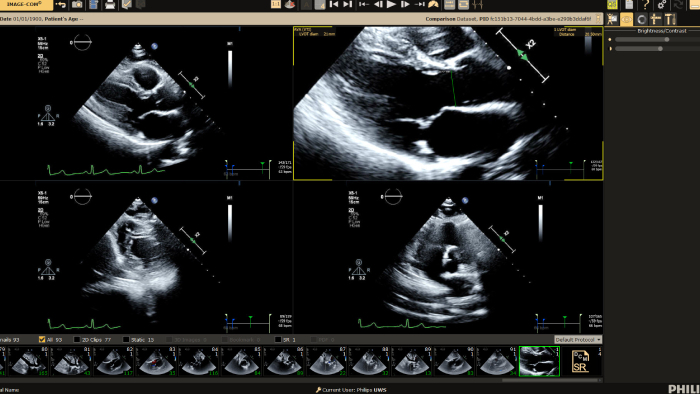

You can still access recordings of 4 full days of hands-on workshops about best practices in multimodality cardiac imaging with expert teams. See first-time-right imaging for cardiac care, including valvular and related diseases, cardiomyopathies, and intracardiac masses and cardiac tumors. Sign up to receive access to these on demand sessions and other news about Philips and cardiac care.

Increase diagnosis confidence and clinical efficiency through superior image quality, advanced quantification tool and automation technology.

Provide a single point of access to patient’s cardiovascular diagnostic information and multi-modality images at excellent diagnostic quality, including prior exams, as well as findings, measurements, and reports.